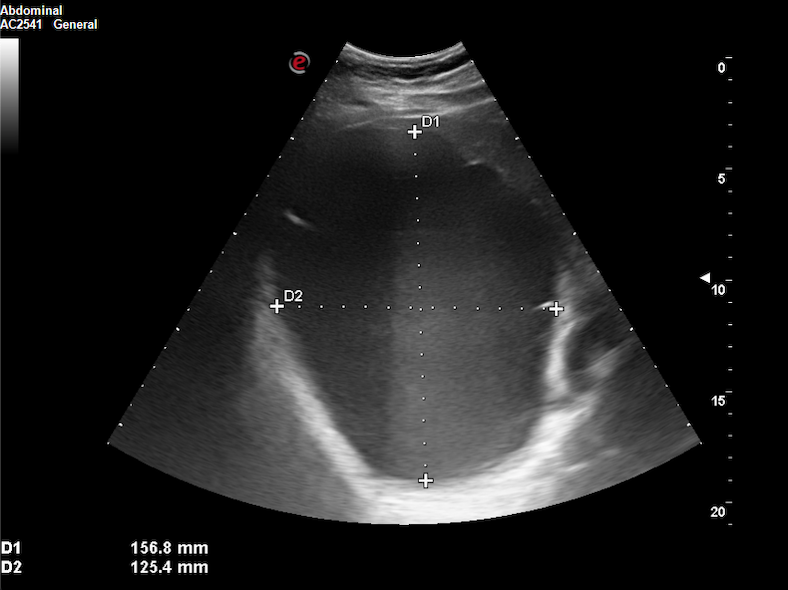

Realizamos ecografía clínica (EC) en nuestro centro de salud, objetivando un quiste de 15 x 12 x 12 cm a expensas de lóbulo hepático derecho, con paredes lisas, refuerzo posterior, contenido anecoico y Doppler-negativo.